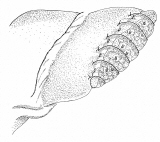

和綴じの方法を応用した、肝部分切除

和綴じの本をお持ちの方は、バラして見るのも一興かも。でも、ご先祖様が化けて出るかも